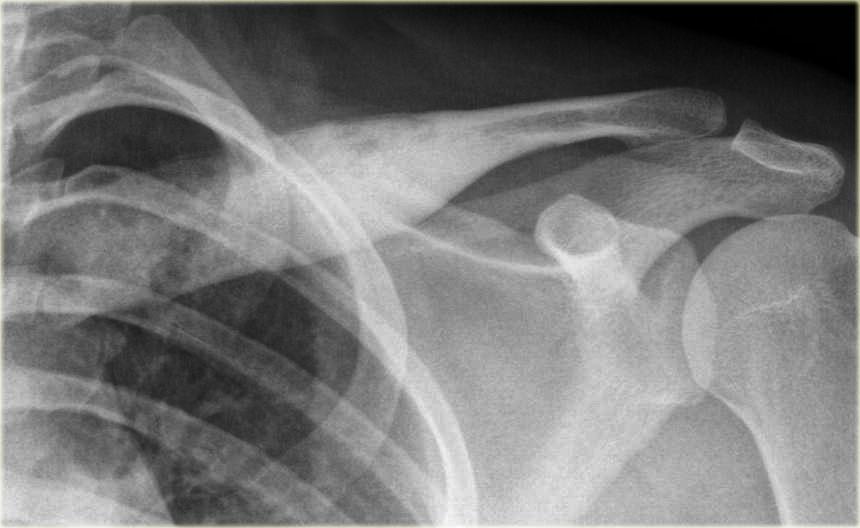

Đây là hình ảnh của một bệnh nhân có khối xơ cứng cạnh vỏ xương ở đầu trên xương cánh tay (trái).

Trường hợp này được xác định là vôi hóa phản ứng thứ phát sau chấn thương.

Lưu ý sự tương đồng với khối u cạnh vỏ xương ở một bệnh nhân khác (bên phải), được chẩn đoán xác định bằng sinh thiết là u xương cạnh màng xương (parosteal osteosarcoma).

Điều này cho thấy rằng việc phân biệt khối u với một quá trình phản ứng đôi khi có thể rất khó khăn trong một số trường hợp.

Khi một quá trình phản ứng có khả năng xảy ra hơn dựa trên tiền sử và đặc điểm hình ảnh, đôi khi vẫn cần theo dõi thêm.